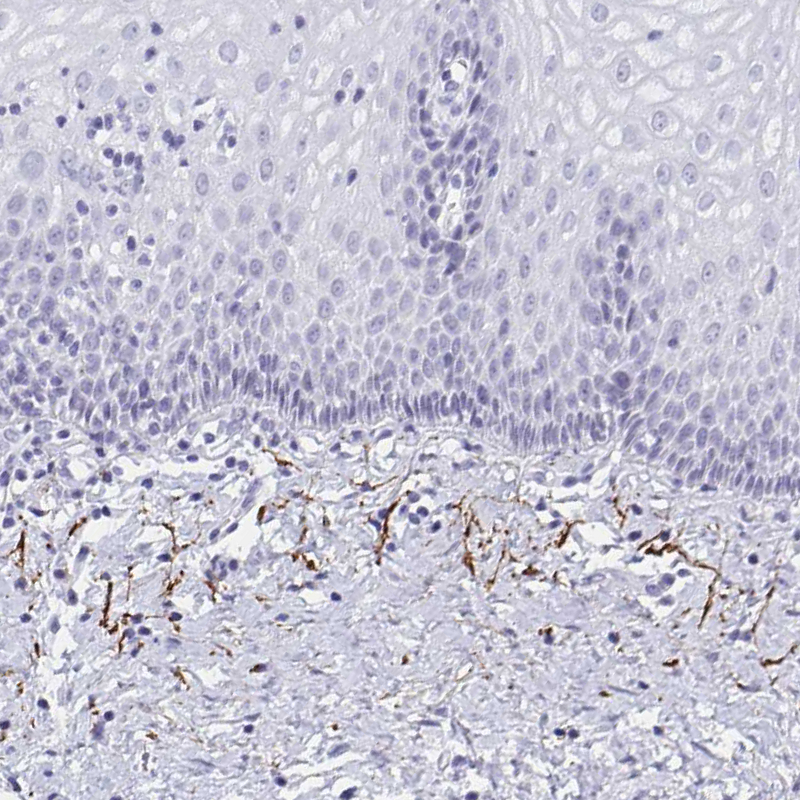

Immunohistochemical staining of human lung shows moderate positivity in the extracellular matrix in blood vessels.